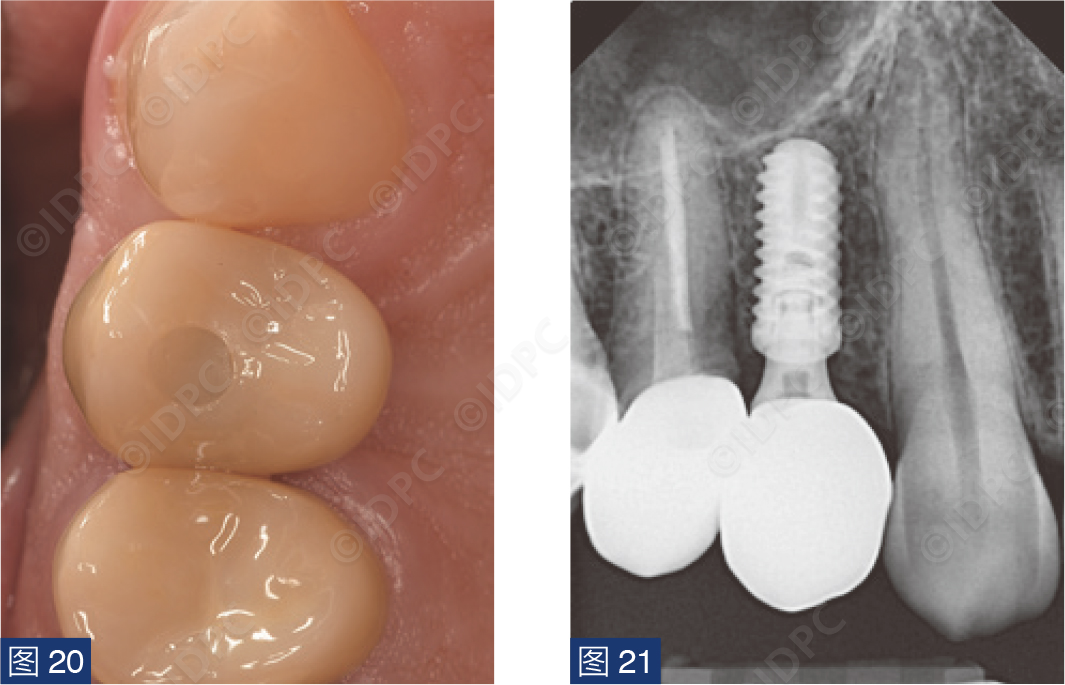

在exocad软件(exocad公司)上进行全数字化修复流程设计,在copaSKY uni.fit钛基底(bredent medical公司)上制作完成螺丝固位氧化锆混合陶瓷一体冠。种植位点显示出足够的颊侧软组织厚度(图12a)及良好的牙龈轮廓(图12b)。取下个性化愈合基台后,种植体周围软组织健康(图13、14),此外,取下后立即进行术前口内扫描以记录软组织轮廓。随后放置扫描体并进行数字印模以记录种植体位置(图15)。同时扫描对颌牙弓及咬合信息。获得的STL文件以数字方式发送至技工室。技工室在钛基底上完成聚甲基丙烯酸甲酯(PMMA)材料的试戴牙冠,以检查邻接和边缘密合情况,同时调整咬合(图16、17)。一旦完成所有调整,进行重新扫描。最终在钛基底上完成螺丝固位的全结构氧化锆混合陶瓷修复体,与牙龈接触的修复体表面高度抛光(图18),并以25 Ncm戴入口内。修复体实现了出色的颜色匹配及临床结果(图19)。螺丝孔用聚四氟乙烯填塞并用树脂材料密封(图20)。术后对照X线片显示修复体正确就位(图21)。六个月复查,增加的软组织轮廓清晰可见,牙槽骨水平保持稳定(图22-24)。

图20:树脂封闭𬌗面螺丝孔。